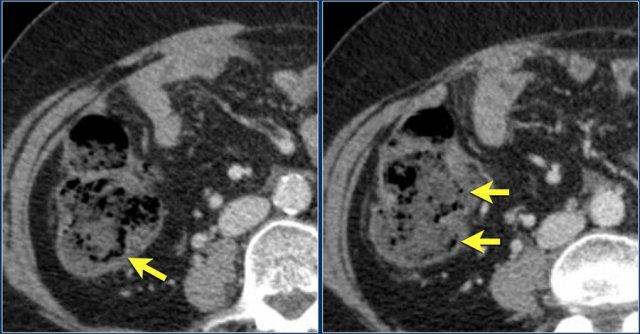

Các hình ảnh này thuộc về bệnh nhân bị tắc ruột non dạng quai kín.

Lưu ý nhóm các quai ruột non có thành dày ở vùng bụng trên phải (mũi tên vàng).

Phù nề mạc treo ruột (mũi tên đỏ) cho thấy tình trạng tăng áp lực tĩnh mạch do thắt nghẹt.

Giãn mạch máu

Tăng áp lực tĩnh mạch trong thắt nghẹt cũng dẫn đến giãn tĩnh mạch (mũi tên vàng).

Bệnh nhân này cũng có tắc ruột dạng quai kín với kiểu ngấm thuốc xám của các quai ruột bị thắt nghẹt (mũi tên đỏ).

Lưu ý sự ngấm thuốc bình thường của ruột non ở phía trên vị trí tắc nghẽn (mũi tên xanh lá).

Một bệnh nhân khác với hình ảnh ruột thiếu máu cục bộ và phù nề mạc treo ruột lan rộng.

Trong phẫu thuật, toàn bộ đoạn ruột non này đã bị hoại tử.

Dấu hiệu phân trong ruột non

Mũi tên màu vàng chỉ dấu hiệu phân trong ruột non ở bệnh nhân tắc ruột non.